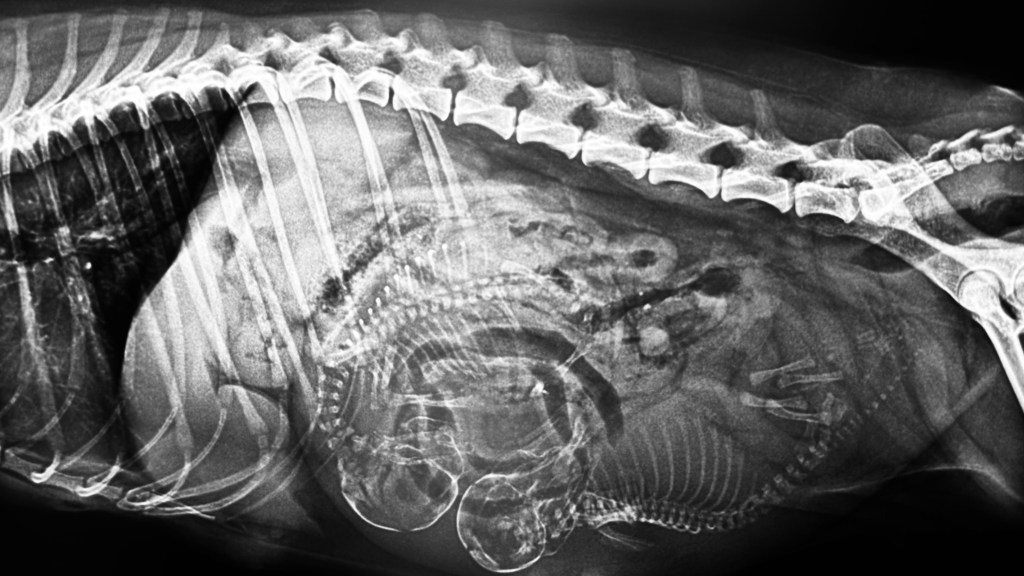

Als wir vor 9 Wochen nach Österreich fuhren, um Paparazzi kennenzulernen, wurde ich Zeugin von Liebe auf den ersten Blick. Céline und Paparazzi passten charakterlich sowie optisch perfekt zusammen. Heute haben wir die Bestätigung durch das Röntgen bekommen. Celine trägt zwei Welpen und wird voraussichtlich am 11. Mai werfen.